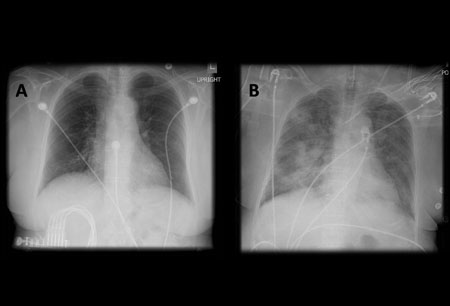

- radiografia torácica

- tomografia computadorizada (TC) do tórax